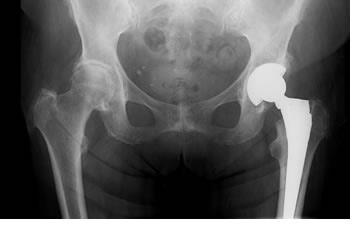

The hip joint is a ball-and-socket joint created by the articulation of the head (ball) of the femur with the concave surface (socket) of the acetabulum. Total Hip Arthroplasty is the surgical treatment that replaces the natural bony articulations with artificial implants. There are approximately 200,000 Total Hip Replacements (THR) performed in the United States per year. Needless to say, this has become a common treatment modality replacing the older procedures of arthrodesis (fusion) and osteotomy.

The stem replaces the femoral head and articulates with the socket. The component also is available in a variety of designs and materials. The stem can be fixed to the femoral host bone by either the use of bone cement or of cementless fixation by press fit or porous ingrowth materials. Most modern day stem devices feature a modular head and some of the newer designs also feature a modular neck or proximal body that provide additional benefits that enable the surgeon to reconstruct proper mechanics of the hip joint.